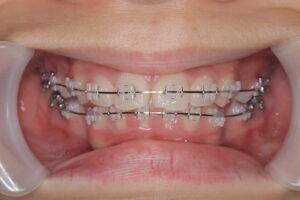

患者さんは、上の前歯が捻れており来院。そこで口呼吸を指摘したところ、以前から気にされていたが矯正で改善出来ることを知って治療を開始することになった。

診断の結果、上下前歯の唇側傾斜を伴う軽度叢生

治療内容:

上下顎左右第一小臼歯(計4本)を抜歯

上下表側のブラケット装置で治療

治療期間は1年9ヶ月

治療中写真

結果:

口元の突出感が改善

患者さんもお母さんも口元の改善にとても喜んでおられました。